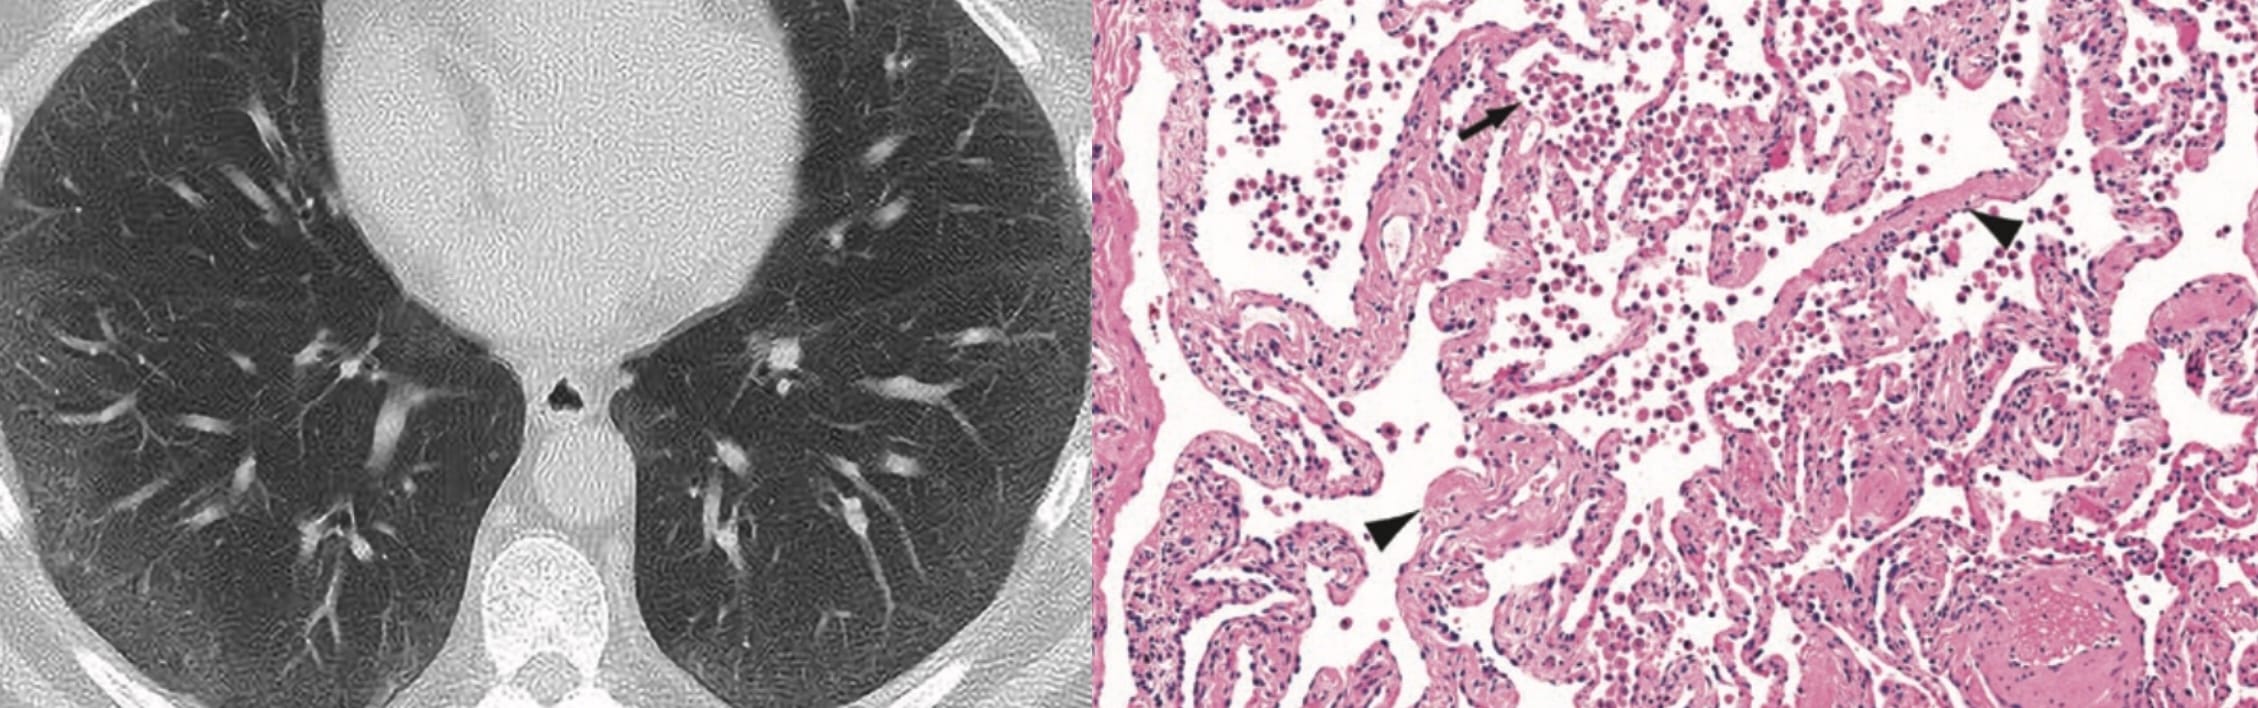

- Usual Interstitial Pneumonia